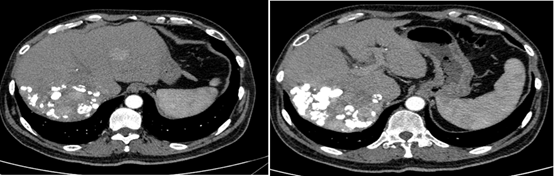

2019年2月21日以碘油5 ml+0.9%氯化钠20 ml+表阿霉素10 mg+雷替曲塞1支稀释后灌注方案行TACE治疗。后复查肝增强CT,未见明显强化,对比2019年1月病灶略缩小,初次TACE治疗达SD。

图片

图:肝增强CT(2019-02-21)